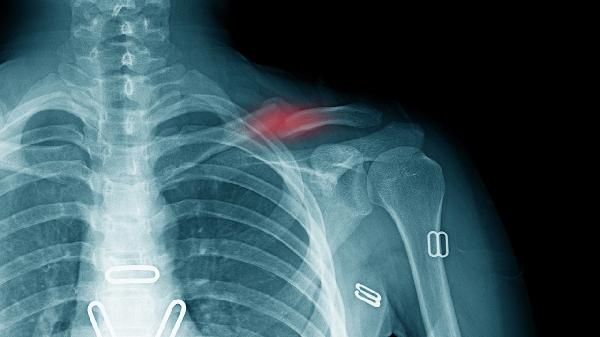

少数情况下需考虑病理性因素。髋关节发育不良者可能在特定体位出现关节半脱位弹响,多伴随关节卡顿感。骶髂关节紊乱患者会有骶骨区域清脆弹响,常与久坐劳损相关。这两种情况均需骨科医生通过触诊和影像学检查确诊,必要时需采用手法复位或佩戴矫形支具。

骨质疏松或应力性骨折虽罕见但需警惕。绝经后女性或长期使用激素者若在性活动中听到断裂声并伴剧痛,可能发生股骨颈或耻骨支骨折。此类情况需立即制动并急诊处理,延误治疗可能导致骨不连等并发症。日常应保证钙质和维生素D摄入,高危人群建议定期骨密度筛查。